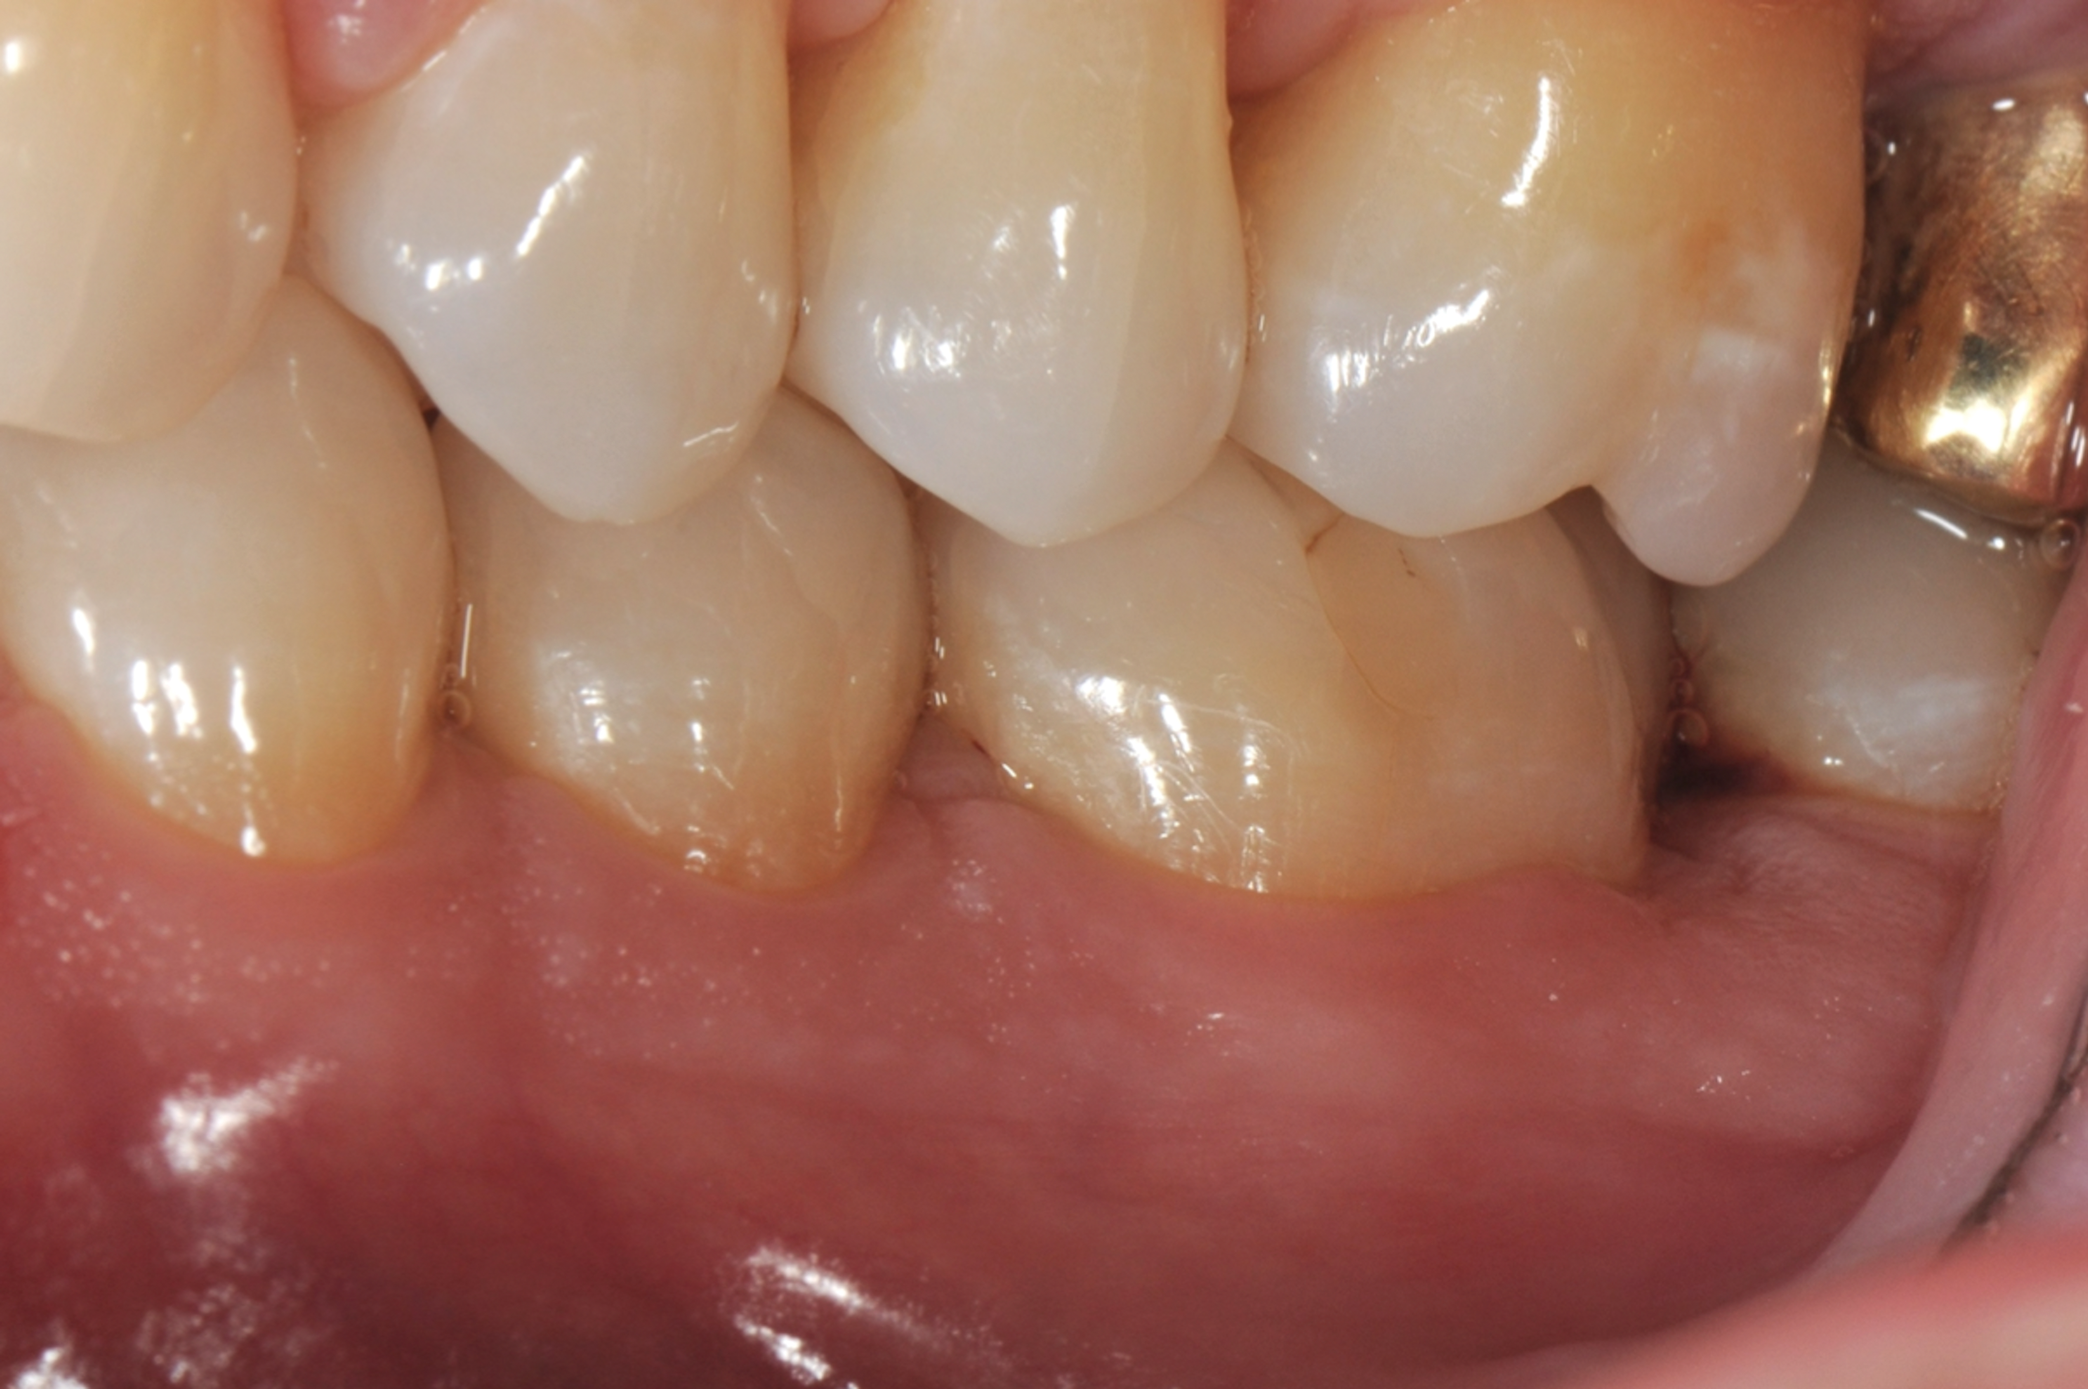

Fig 2. Tooth No. 19 at presentation, occlusal view. Note the thickness of the soft tissue and width of keratinized tissue.

Figure 2

In the case presented, a 56-year-old healthy nonsmoking male patient, diagnosed with periodontitis stage III, localized, grade B, had been under care in a private practice periodontal office (RAL) for 25 years. He had a history of good compliance with his treatment (full-mouth plaque score <20%). During the COVID-19 pandemic, the patient missed three supportive periodontal therapy (SPT) visits over a year, resulting in periodontal breakdown interproximal between teeth Nos. 18 and 19 (mandibular left second and first molars, respectively). At his most recent periodontal maintenance visit, significantly increased periodontal probing depths of up to 10 mm with bleeding on probing were noted (Figure 1 through Figure 3). The periapical radiograph revealed a deep, narrow three-wall intrabony defect at the distal aspect of tooth No. 19, with class I buccal furcation involvement (Figure 4). According to the periodontal risk score (PRS),15 formerly known as the Miller-McEntire periodontal prognosis index, the tooth prognosis at the patient's initial examination was "good" (score = 5), taking into account that he was unaware of his hemoglobin A1C (HbA1c) levels. This scoring motivated the patient to be tested, and his follow-up HbA1c was <6%, thus reducing his PRS to 3, which was considered "excellent," as the PRS target goal for regenerative procedures is a score of <5.15

Tooth No. 19 presented with no mobility and tested vital endodontically. Soft-tissue anatomy was intact, with a keratinized tissue width of >2 mm. The operator was experienced, with no environmental stress and used checklists. Thus, based on the presurgical risk assessment, the patient presented a low-medium risk for periodontal regenerative therapy (Table 2).